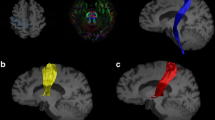

Comparison of the skeletonized FA longitudinally in the iRBD cases revealed reduced FA in the subcortical motor WM of the precentral gyrus as well as in the superior longitudinal fasciculus and corpus callosum (red-yellow in Fig. 1a, corrected p < 0.01), suggesting deteriorating axonal integrity and/or myelination in motor and other WM tracts during the conversion period to motor PD. Follow-up comparison between iRBD and controls showed bilateral loss of DAT binding (as expected, see representative PET images and data in Supplementary Fig. 3, online resource) as well as significantly higher skeletonized FA in the right corticospinal tract during the conversion period to motor PD (Fig. 1b). While all subjects were right-handed, there were no differences between left and right basal ganglia DAT binding dysfunction (between sides p = 0.71 for caudate and p = 0.90 for putamen). The selective change in the right corticospinal tract may imply that structural modification firstly occurs to compensate for the control of the less motor skilled and used left-sided limbs. In the whole brain FA comparisons, the iRBD cases had higher FA values than controls, concentrating bilaterally in the paracentral lobules, but also seen in the middle cingulate cortex, basal ganglia, cerebellum, and pons (Fig. 1c). Overall, there is evidence of early DTI abnormalities in the motor cortex and WM tracts during the conversion period to motor PD and before a diagnosis of PD can be made.

Microstructural changes in the motor system of longitudinally followed iRBD cases that progressed to silent and/or prodromal motor PD. a Longitudinal fractional anisotropy (FA) changes in the iRBD group (n = 8). Blue lines illustrate the mean skeletonized FA of WM across the two visits. White arrows point to the anatomical location of the cortico-spinal tract. Colour bars represent corrected p values (Follow-up < baseline) by threshold-free cluster enhancement with 10,000 permutations. No significant voxel was found for Follow-up > baseline. b Skeletonized FA comparison between iRBD and controls at follow-up. Blue lines illustrate the mean skeletonized FA of WM across the two groups. Colour bars represent corrected p values for iRBD > healthy controls by Threshold-Free Cluster Enhancement with 10,000 permutations. The threshold p value for comparison of the upper row was 0.05 and of the lower row was 0.1. No significant voxel was found for iRBD < healthy controls. c Whole-brain FA comparison between iRBD and controls at follow-up. Blue and yellow shadows indicate right and left paracentral lobules, respectively, which contain the primary motor cortex sampled in our post-mortem study. Colour bar represents the corrected p values for iRBD > healthy controls by Threshold-Free Cluster Enhancement with 10,000 permutations. No significant voxel was found for iRBD < healthy controls. x, y, and z are MNI (Montreal Neurological Institute) coordinates in the standard space. x ranges from 0 to 181 as from right to left. y ranges from 0 to 217 as from posterior to anterior. z ranges from 0 to 181 as from bottom to top. White arrows in a and b point to the anatomical location of the cortico-spinal tract. Abbreviations: Follow-up < baseline: iRBD group had decreased FA in the longitudinal analysis, Follow-up > baseline: iRBD group had increased FA in the longitudinal analysis, iRBD > healthy control group: iRBD group had higher FA than that of healthy control group, iRBD < healthy control group: iRBD group had lower FA than that of healthy control group